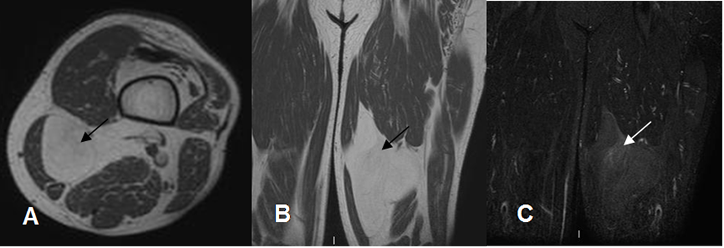

Fig 161. Lipoma.

A: RM axial en T1, B: RM axial en T2 y C: RM axial en STIR. Lesión ovalada y encapsulada en la parte interna del pie, hiperintensa en T1 y T2 y que suprime en STIR, que corresponde a lipoma.